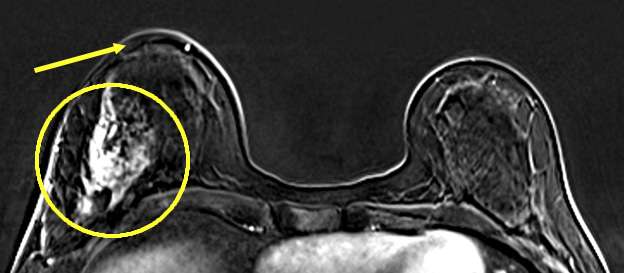

Case: Skin and Nipple Changes Figure 7

Figure 7: Skin Thickening on MRI. Axial contrast enhanced subtracted MR image demonstrates a large area of non-mass enhancement involving the right superior and inferior lateral breast with extension to the axillary tail (circle). Thickening of the overlying skin can also be appreciated (arrow). Findings were consistent with biopsy proven intraductal carcinoma.